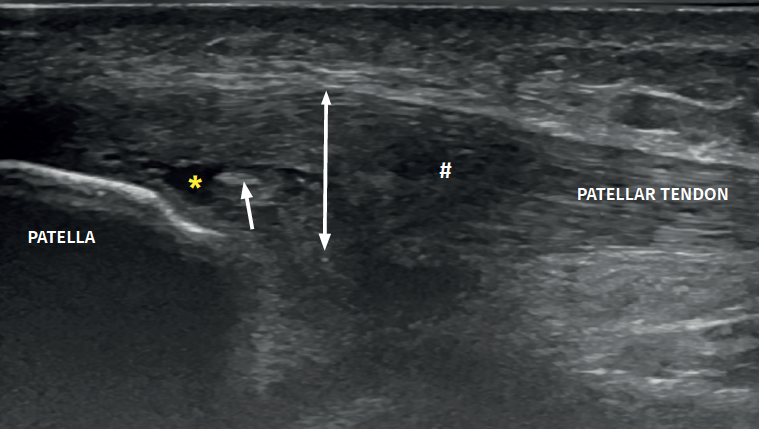

The ultrasound study of a damaged tendon evidences hypoechogenicity and loss of the fibrillar pattern, the appearance of disorganised connective tissue, and thickening of the tendon (Figure 3). In some cases we observe well delimited hypoechoic images indicating intra-substance rupture with nodular or fibrillar shapes, commonly manifesting in the deepest zone of the tendon in the lower pole adjacent to the patella (Figure 4).

Figure 4. High-resolution ultrasound study of patellar tendinopathy. Linear probe with longitudinal view. The double arrow shows increased tendon thickness, with hypoechogenic altered fibrillar pattern (#), intra-substance rupture (asterisk) and fibrosis (arrow).

In the middle portion of the tendon we may observe thickening (> 3.5 mm) associated to hypoechoic areas with zones of disorganised collagen and loss of the fibrillar pattern.

It is also common to identify cortical irregularities in the proximal enthesis of the tendon at the point where it joins the patella, involvement of the paratendon and adherences to Hoffa's fat pad. Any calcifications will be seen as white hyperechogenic zones (Figure 5).